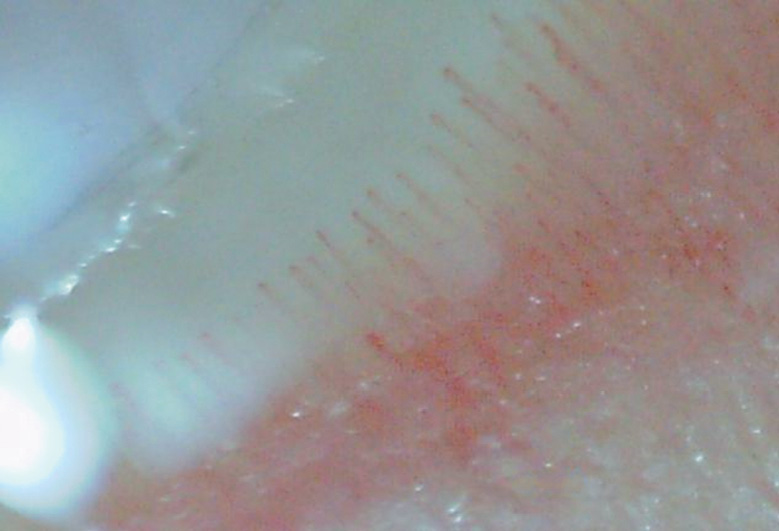

In the comparison groups, the capillaroscopic pattern was represented by single pathological changes in the capillaries that did not indicate pathognomonic sclerodermic patterns, except for the group with dermatomyositis/polymyositis where significant Raynaud’s syndrome was diagnosed in two patients (Figs. 6–9).

Fig. 8. Pathological changes of the capillary bed in the group of patients with rheumatoid arthritis

Рис. 8. Патологические изменения капиллярного русла в группе пациентов с ревматоидным артритом

In 20 patients with rheumatoid arthritis, NFC revealed capillary dilatation (n = 3) and pathological tortuosity (n = 4) in all study fields. These abnormalities are clinically insignificant and may be associated with the initial manifestations of digital vasculitis.